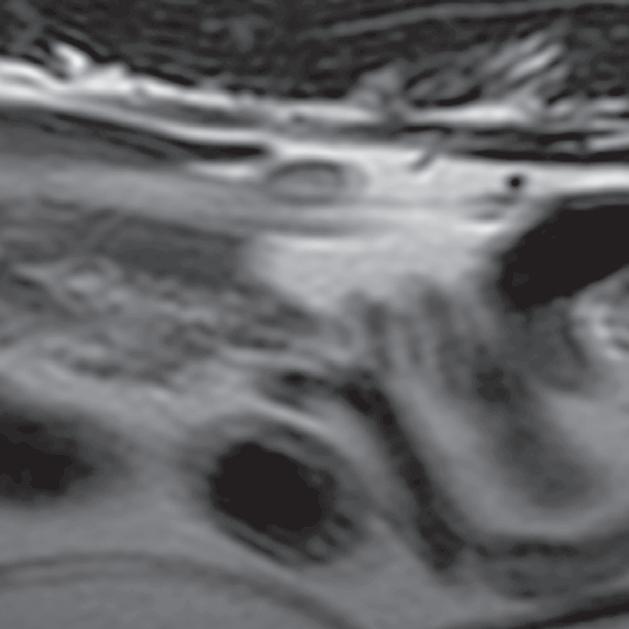

Rycina

3.2.8. Podwichnięcie kręgów szyjnych ze złamaniem wyrostka stawowego (pies) TK i MR

Badania wykonano u 5-letniej samicy mieszańca w typie teriera, która została pogryziona w okolicy szyjnej przez większego psa tego samego dnia, w którym wykonano badania. Podczas wizyty u psa zaobserwowano deficyty neurologiczne z neuroanatomiczną lokalizacją w obrębie C6–T2. Radiogramy przeglądowe ukazały grzbietowe podwichnięcie kręgu C7 względem C6 oraz zwężenie przestrzeni międzykręgowej C6–C7 (a – grot strzałki). Podobne zmiany uwidoczniono na obrazach TK w projekcji strzałkowej i 3D (b, f – grot strzałki). Dodatkowo stwierdzono wieloodłamowe złamanie z przemieszczeniem prawego doczaszkowego wyrostka stawowego kręgu C7 (c–e – strzałka). Dla porównania przedstawiono prawidłowy lewy wyrostek stawowy (f – strzałka). W badaniu MR przestrzeń międzykręgowa C6–C7 była zwężona i wykazywała obniżoną intensywność sygnału w obrazach T2-zależnych (i – strzałka), a przemieszczony materiał dyskowy znajdował się w prawej dobrzusznej części kanału kręgowego (g, h – grot strzałki). W obrazach występują cechy ucisku na rdzeń kręgowy (g–i) oraz zwiększona intensywność sygnału w sekwencji T2-zależnej w obrębie rdzenia na poziomie C6–C7 (h, i), co wskazuje na jego uszkodzenie wewnętrzne. Materiał dyskowy został chirurgicznie usunięty z kanału kręgowego, a podwichnięcie zredukowano i ustabilizowano operacyjnie